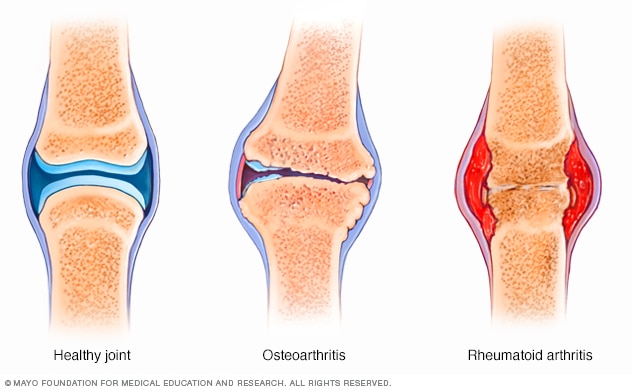

Radang Sendi, Penyebab Utama Nyeri Lutut pada Lansia

Radang Sendi, Penyebab Utama Nyeri Lutut pada Lansia

Kenali Penyakit Nyeri Sendi Osteoartritis, Ini Penyebab, Gejala, Stadium dan Pencegahannya - Halaman all - Tribun Jabar

Kenali Penyakit Nyeri Sendi Osteoartritis, Ini Penyebab, Gejala, Stadium dan Pencegahannya - Halaman all - Tribun Jabar

Kenali Penyakit Nyeri Sendi Osteoartritis, Ini Penyebab, Gejala, Stadium dan Pencegahannya - Halaman all - Tribun Jabar

Kenali Penyakit Nyeri Sendi Osteoartritis, Ini Penyebab, Gejala, Stadium dan Pencegahannya - Halaman all - Tribun Jabar

Penyakit Radang Sendi: Jenis, Gejala, Penyebab, dan Pengobatannya

Penyakit Radang Sendi: Jenis, Gejala, Penyebab, dan Pengobatannya